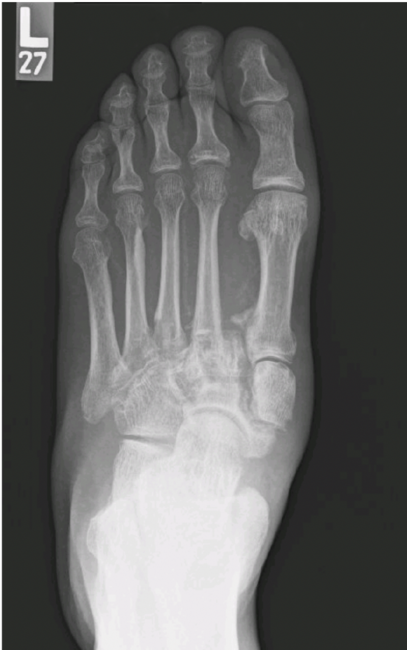

A 58-year-old man with type 2 diabetes, peripheral neuropathy, and diabetic nephropathy presented to our outpatient clinic with increasing pain and deformity of the left foot. He had no history of trauma and denied having any constitutional symptoms. His most recent hemoglobin A1c was 8.1%. The physical exam revealed a warm and well-perfused foot with palpable and Dopplerable pulse, but the left foot had increased asymmetric warmth compared to the right. There were no open wounds. However, he presented with a rocker-bottom configuration confirmed by radiographs with a negative talometatarsal angle and appreciated ptosis of the cuboid below the midfoot horizon.

Plain radiographs of the foot revealed advancing destruction and diastasis across the tarsometatarsal joint complex and subluxation of the midtarsal complex. Given the complexity of the deformity in multiple planes and likely progression to an unbraceable foot, we offered the patient an acute correction. Stage 1 would be through a butted frame with hexapod configuration followed by consideration of intramedullary fixation as a second stage if necessary.

diastasis across the tarsometatarsal joint complex and subluxation of the midtarsal complex.